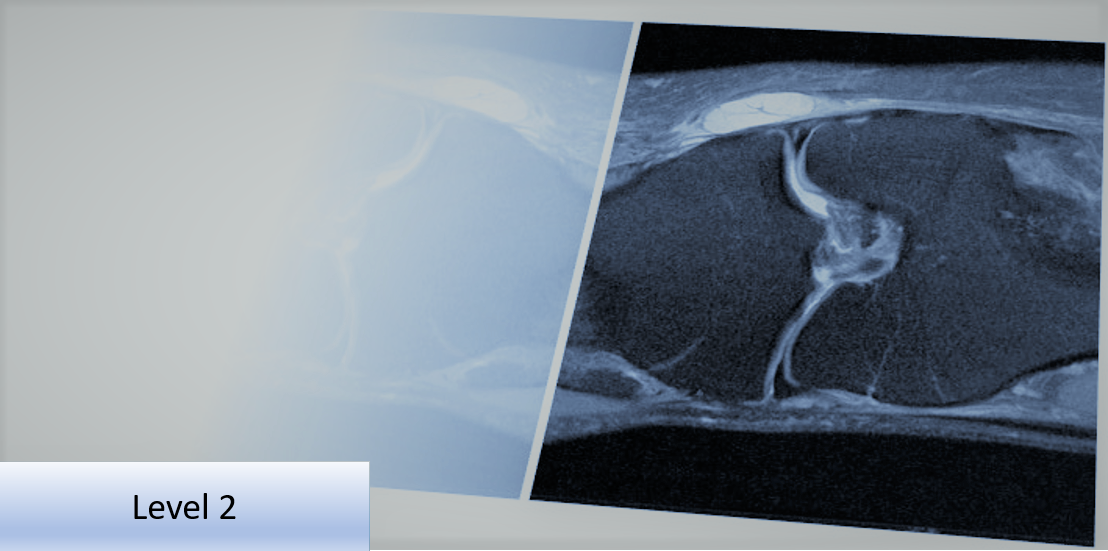

Level 2 Further Skills: Musculoskeletal Imaging Referral and Interpretation - Lower Limb

This Level 2 course will provide the delegate with further skills and understanding to improve diagnostic imaging use and ensure it is clinically appropriate, thereby supporting clinical examination of the lower limb.

Each course uses case studies to investigate relevant common conditions and pathologies with clinical presentations and associated imaging.

Common conditions, and injuries plus structures involved in lower limb. Impact on the clinical examination